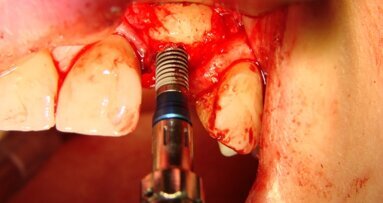

W znieczuleniu miejscowym odwarstwiono płaty pełnej grubości, uwidaczniając zadowalający stopień regeneracji wyrostka szczęki (Ryc. 8 i 9). Wykręcono śruby namiotowe (Ryc. 10 i 11) i przy użyciu szablonu chirurgicznego wprowadzono implanty Astra 3,5 x 13 mm w pozycjach 16, 15, 25 i 26 oraz implanty Astra 3,5 x 11,5 w pozycjach 14 i 13. Następnie implanty zaopatrzono w filary typu Uniabutment 20 st. o 3 mm wysokości. Ranę zaopatrzono szwami 4/0 Safil (Ryc. 12 i 13). Do filarów dokręcono tuleje i osadzono protezę, wykorzystując klucz zwarciowy dla uniknięcia dyslokacji uzupełnienia. Po polimeryzacji kompozytu łączącego (LuxatempFluorescence, DMG), zredukowano płytę protezy do mostu typu FixedDetachableProsthesis (Ryc. 14 i 15).